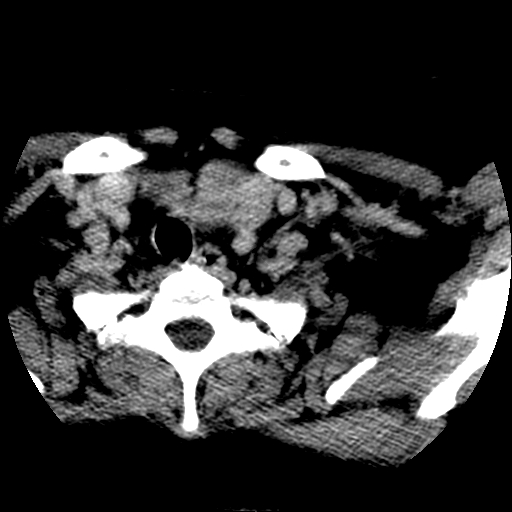

左右叶都有,峡部也受累,有钙化,考虑结甲可能性大。

考虑右叶结节性甲状腺肿,伴左叶钙化。主要(1)密度均匀,边境清。(2)病灶与血管界限清。